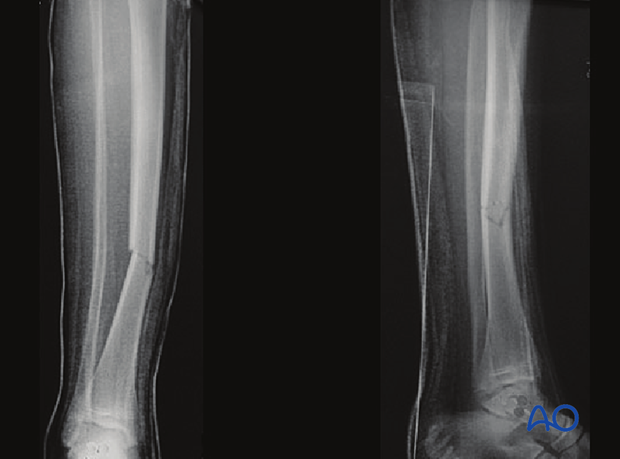

Case example of an oblique tibial shaft fracture

Application of articulated tension device

Final reduction against the plate

Completed fracture fixation